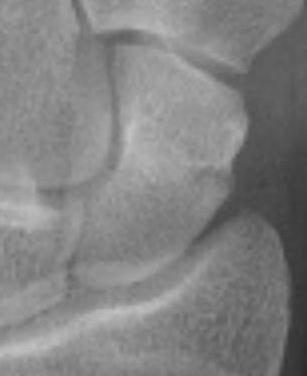

X-ray

5 images

- PA / lateral

- PA in 45° oblique pronation / PA 45o oblique supination

- PA in ulna deviation